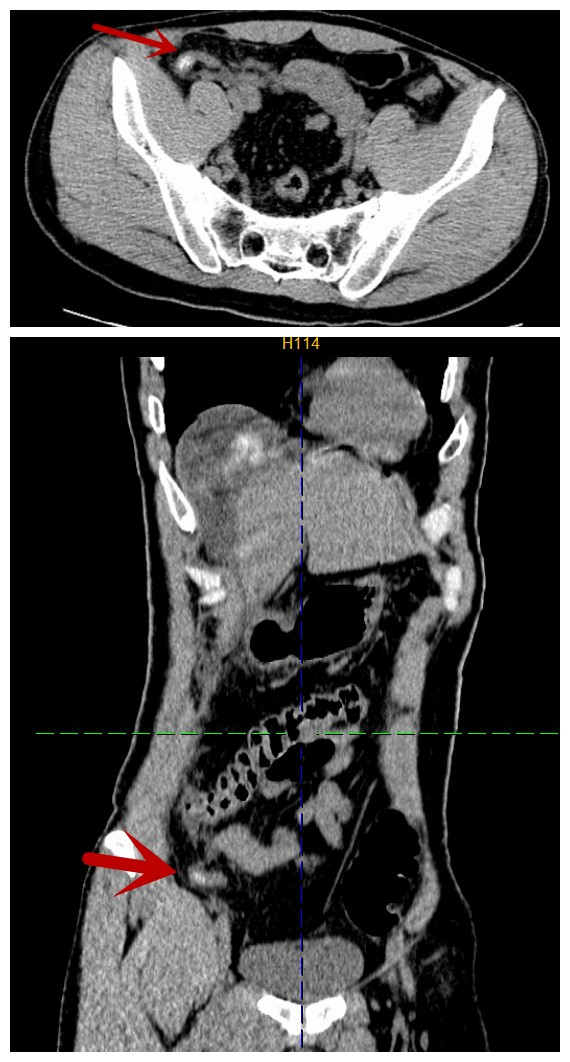

术前CT,箭头所指为阑尾肿胀伴有粪石

37岁男性患者唐某,因突发腹痛8小时于2026年1月8日急诊入院,呈刀割样剧烈疼痛,难以忍受。入院查体:急性病容,腹肌紧张,上腹部、右上下腹部压痛、反跳痛明显,肠鸣音减弱,约1次/分。腹膜炎体征明显,入院予急诊完善腹部CT检查提示:1.气腹,考虑消化道穿孔。2.阑尾粪石,并阑尾炎。3.腹腔积液。因病变部位不同,胃穿孔的病变解剖部位在上腹部,阑尾炎的病变解剖部位在右下腹,考虑要兼顾上下腹、充分显露手术部位等,传统手术需在腹壁开10cm-15cm的较长切口,手术创伤大,恢复慢。医生决定采用腹腔镜手术,只在腹壁打3-4个0.5cm-1.0cm戳孔就能完成手术。

诊断明确,完善术前准备后,患者急诊送手术室。由普外科一病区副主任、主任医师韦义伦主刀,在全身麻醉下行腹腔镜探查。术中腹腔镜下探查见肝周、腹盆腔广泛积黄色混浊脓性液约800ml,腹腔内见脓苔附着,腹膜炎性充血潮红,胃幽门管前壁见一直径约0.8cm溃疡穿孔,周围组织稍水肿,大网膜、小肠与右上腹壁粘连,肝脏未见异常,腹、盆腔未见异常结节。回肠与右下腹壁粘连,阑尾位于盲肠下方,尖端指向盆腔,阑尾长约8cm,直径约1.5cm,明显充血肿胀,表面覆有脓苔,阑尾腔内有多粒粪石,最大的大小约1.5×1.2cm。予行腹腔镜下胃幽门管前壁溃疡穿孔修补术+溃疡活检术+阑尾切除术+肠粘连松解术+腹、盆腔冲洗引流术,手术耗时2小时余,术后恢复快,术后4天恢复流质饮食,术后5天出院。